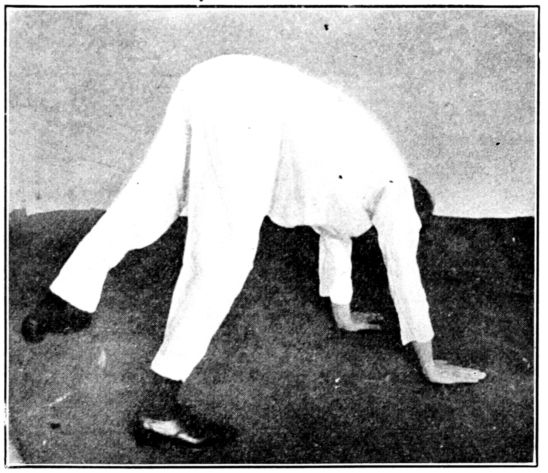

| 136. | Knee-chest position | 354 |

| 137. | Exercising by walking on all fours | 354 |